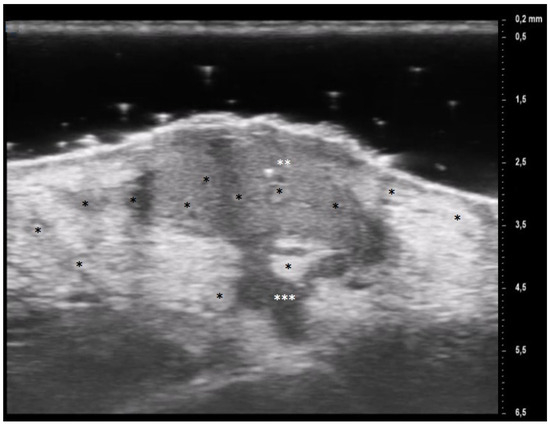

A comprehensive patient’s assessment was performed at T0 and T1. The clinical investigation was performed by a dermatologist expert in pyoderma gangrenosum which collected a photographic record of the patient and assessed clinical disease parameters such as pain, measured with VAS. UHFUS investigation was performed by a dermatologist expert in UHFUS blinded from the clinical diagnosis by three UHFUS clips with a 70 MHz linear probe (Vevo MD® FUJIFILM VisualSonics, Toronto, Ontario, Canada), in B-MODE. The use of UHFUS with a 70 MHz probe allows to examine the more superficial cutaneous and adnexal features with a spatial resolution in the order of 30 μm (Figure 1). A correlation between digital photograph and US clip was performed: two regions of interest (ROI) at the wound bed and edge were provided for the ulcerative phenotype, while one ROI was provided for the pustular phenotype. The probe was placed perpendicular to the lesion and a large amount of gel was used to maintain the adequate distance from the skin surface. The US parameters (such as gains, depth, time gain control, focus) were optimized during the examinations. A qualitative-quantitative analysis of the US features was performed by 2 dermatologists experienced in UHFUS imaging.

Figure 1. UHFUS features of healthy skin: epidermis (*), dermis (**) and hypodermis (***).